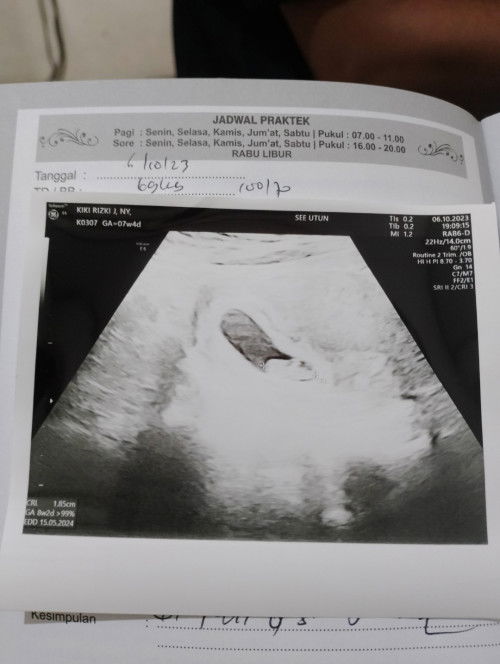

Bun aq 6w blm periksa tapi sudah konsumsi vitamin folavit 400mcg bagus ga ya bun .#seriusnanya Trus di minumnya sehari brpx